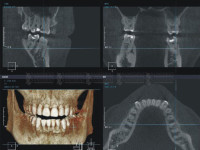

2. Трехмерная компьютерная томография (КТ).

Трехмерная компьютерная томография — это специализированное программное обеспечение компьютерная томография (КТ) позволяет с поразительной точностью определять все основные факторы для диагностики и планирования операции по дентальной имплантации.

Далее приведем список основных параметров и манипуляций с КТ.

- Позволяет определить точный уровень костной ткани в предполагаемом месте установки импланта.

Дает возможность изучить область верхней челюсти а именно области гайморовых пазух, тем самым предотвратить возможную установку имплантатов в гайморову пазуху. - Позволяет хирургу использовать внушительный арсенал инструментов (таких как «линейка») для просчета, измерения и диагностики объектов, учитывая их реальные размеры и расположение.

- Так же, программа с легкостью позволяет разместить импланты в запланированных местах виртуально, предоставляя полный обзор их возможного размещения.

- Компьютерная томография (КТ)